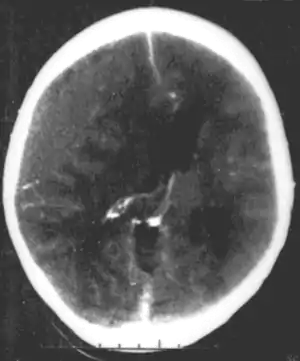

CT scan showing epidural hematoma, a type of traumatic brain injury (upper left)

Brain trauma in the developing human is a common cause (over 400,000 injuries per year in the US alone, without clear information as to how many produce developmental sequellae)[41] of neurodevelopmental syndromes. It may be subdivided into two major categories, congenital injury (including injury resulting from otherwise uncomplicated premature birth)[6] and injury occurring in infancy or childhood. Common causes of congenital injury are asphyxia (obstruction of the trachea), hypoxia (lack of oxygen to the brain), and the mechanical trauma of the birth process itself.[42]